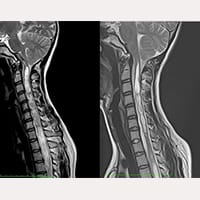

我们是一家位于西班牙巴塞隆纳的国际专科医疗中心,不设分院,专注于精准且高品质的医疗照护。我们采用微创手术从病因治小脑扁桃体下疝第一型、特发性脊髓空洞症与脊柱侧弯等相关疾病,致力于为来自世界各地的患者带来更安全、更有效的治疗选择。